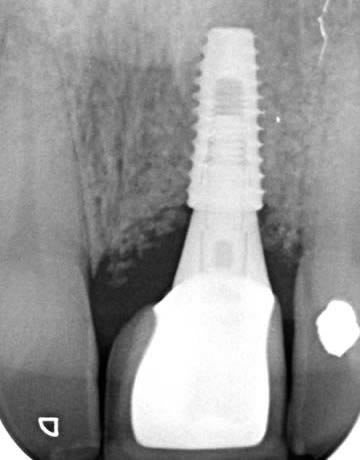

This gentleman had lost his heavily restored UL4 and decided to close the space with an implant retained crown. The thin buck-palatal width required careful placement to avoid fenestration bucally. A tooth bourn position guide was used to place the implant predictably and within the aesthetic envelope. The implant was restored after three months of osseointegration with a bonded crown.